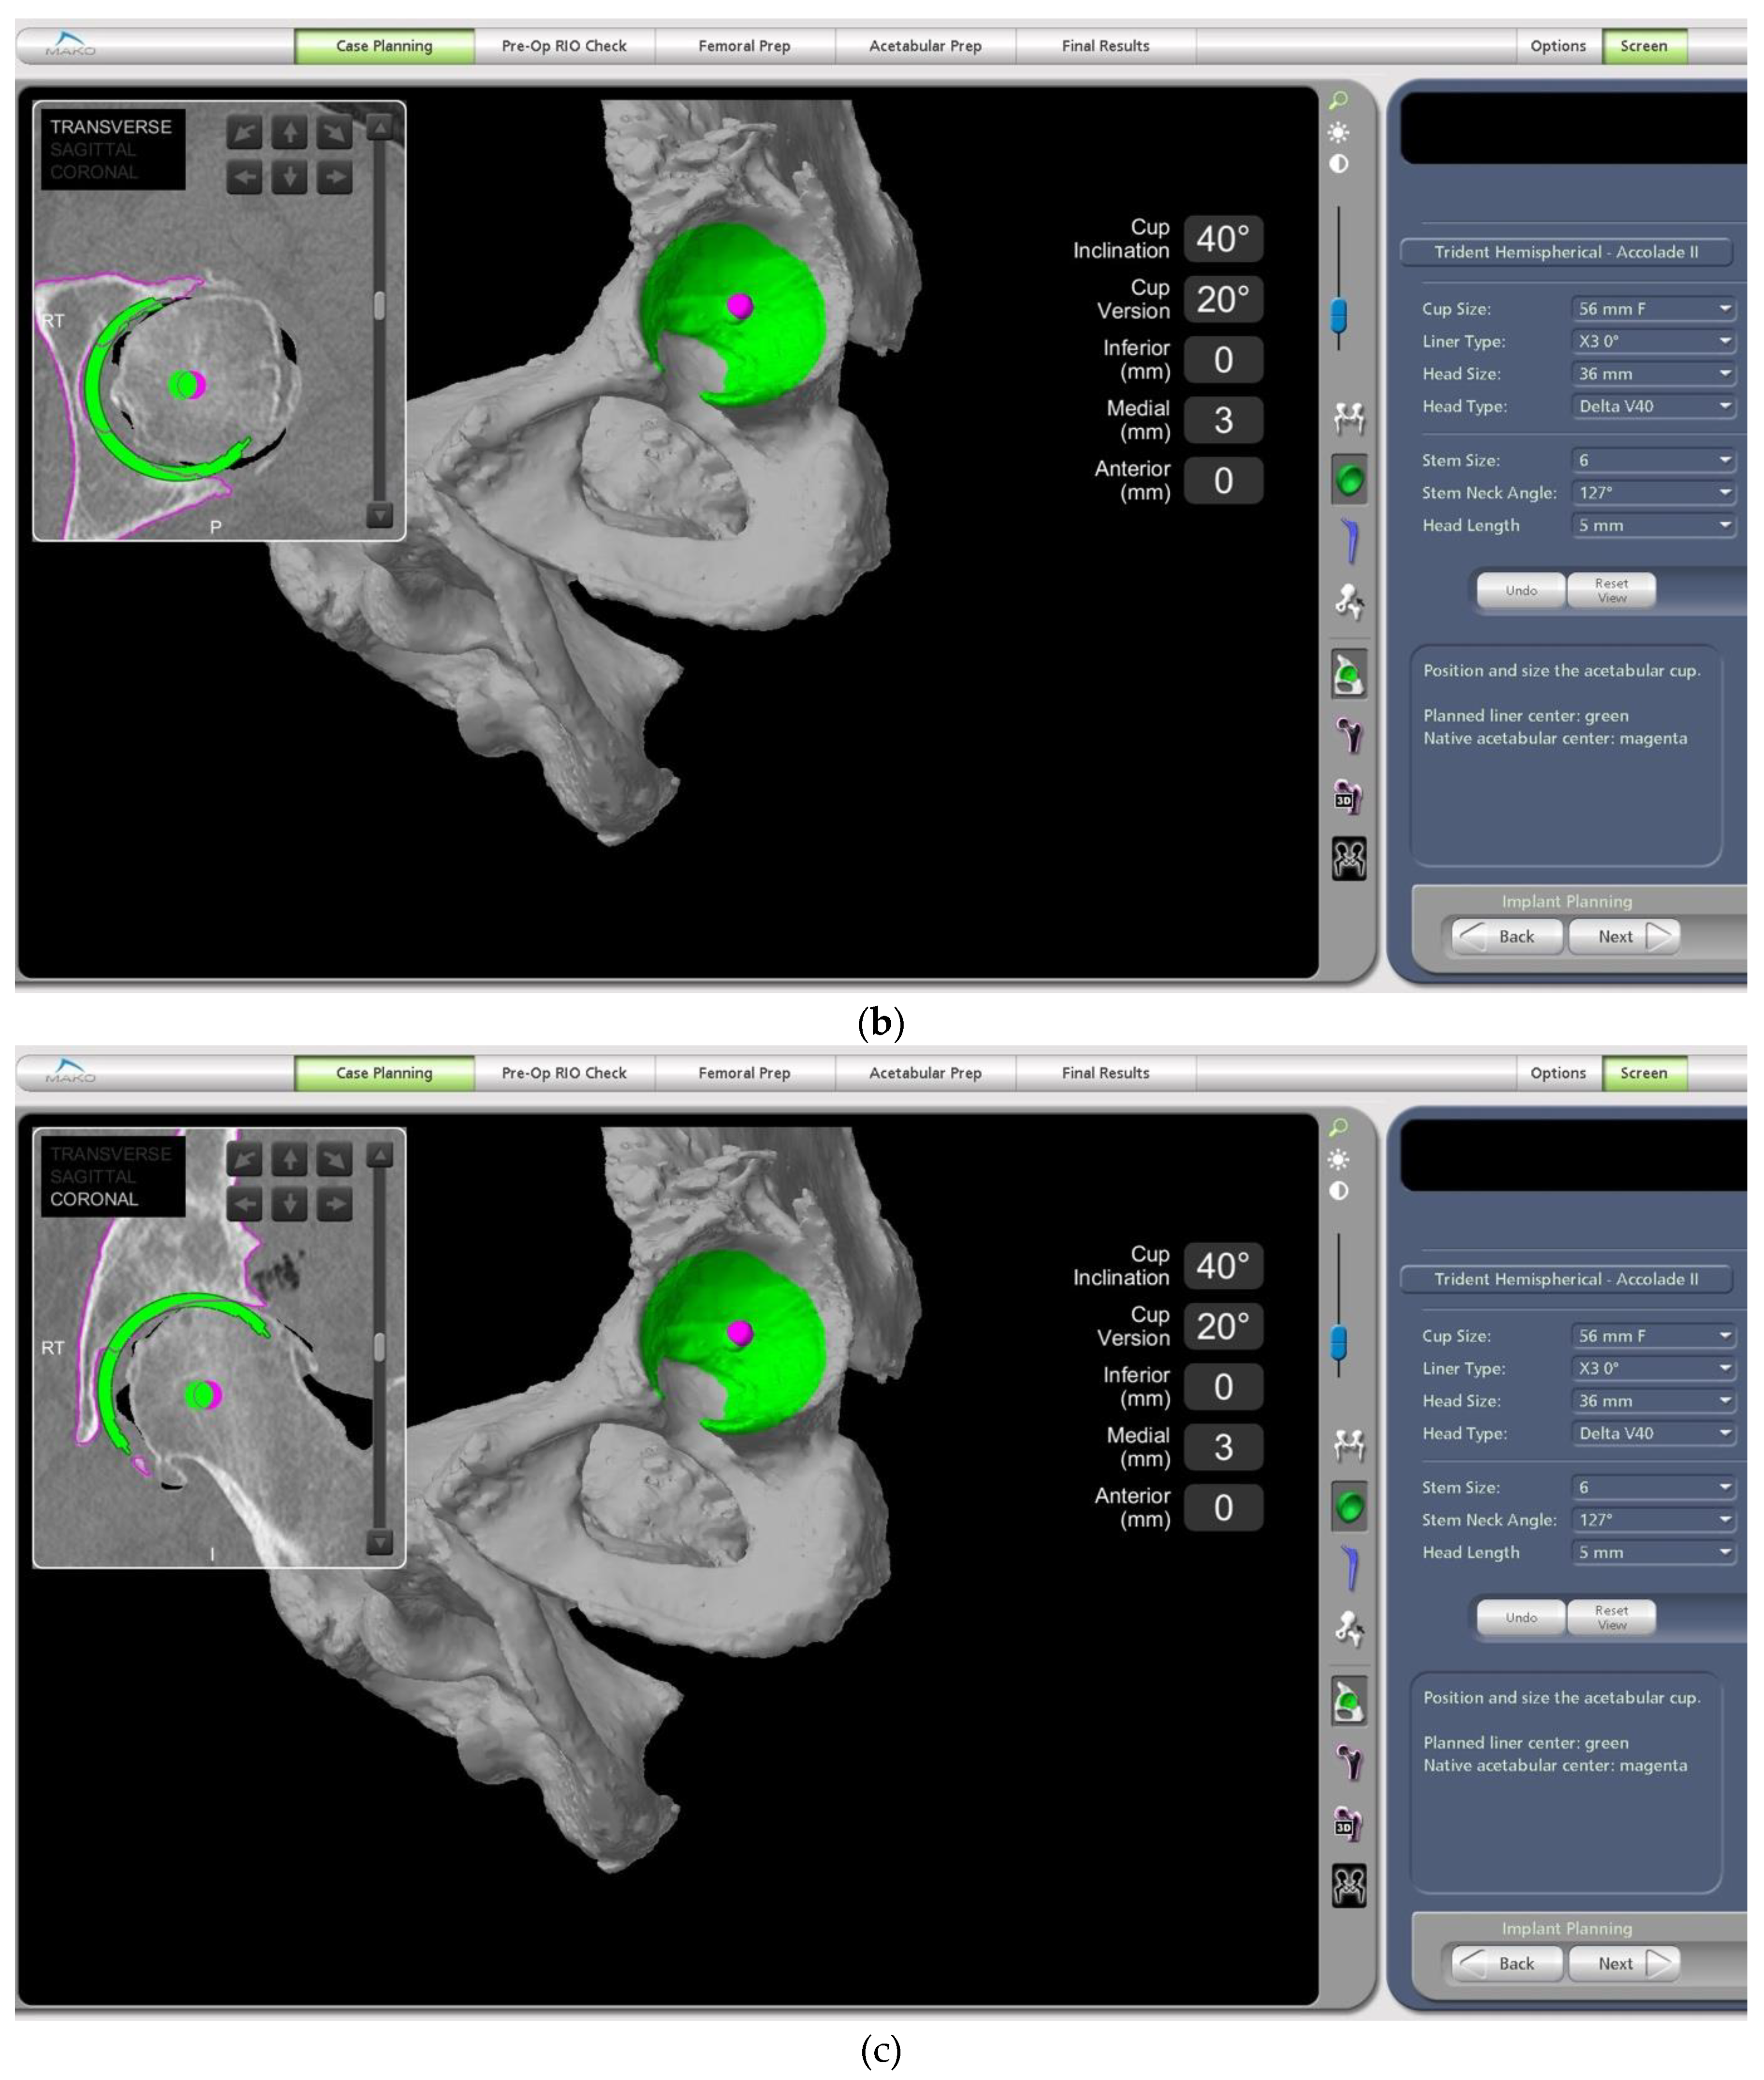

- The difference in sacral slope between standing and sitting radiographs was noted to be 6 degrees. According to the Stefl classification, this is stuck sitting, as the sacral tilt does not tilt anteriorly beyond 30 degrees with standing, indicating a high-risk patient (Figure 6a–c).

- In this case, the native femoral retroversion (−6 degrees) posed a challenge in avoiding impingement (Figure 7). Upon assessing VROM, bone-on-bone and implant-on-implant impingement in deep flexion were noted (Figure 8). Using the robotic software, the planned femoral version was corrected to +16 in the femoral broach (Figure 9a,b).

- The robotic software also enables preoperative and intraoperative visualisation of the anticipated postoperative X-rays accounting for any changes to the plan. In addition, the software allows for calculation of changes to the leg length offset compared to the preoperative and contralateral hips. In this case, the leg length was 1 mm longer compared to the opposite hip, and the combined offset was 6 mm increased compared to that preoperatively (Figure 12a,b).